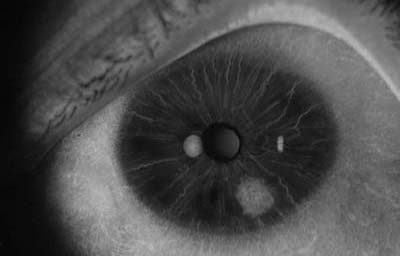

Hamartomas - Nódulos de Lisch. Son estructuras benignas, nodulares, de aspecto gelatinoso, implantadas con pedículo sésil sobre la superficie de la hoja anterior del Iris, compuestas por proliferación de células histológicamente maduras, de origen melanocítico normales del tejido en el que residen, de color que varía del castaño claro al castaño oscuro y generalmente de ± 1.0mm. Cuando se asocian a la Neurofibromatosis de Von Recklinghausen, se las considera patogneumónicas y se las denomina nódulos de Lisch (24, 25,26)

Hamartoma del Iris

Archivo Fotográfico Dr. Carmen Barraquer.

Nódulos de Lisch

Archivo Fotográfico Dr. Francisco Barraquer.

Nódulos de Lisch

Archivo Fotográfico Dr. Francisco Barraquer.